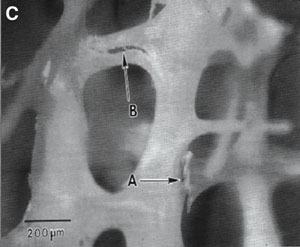

2: Bone in osteoporosis

C. Microcracks in the trabeculae (arrows) (reprinted from Fyhrie and Schaffler, 9 with permission from Elsevier). |